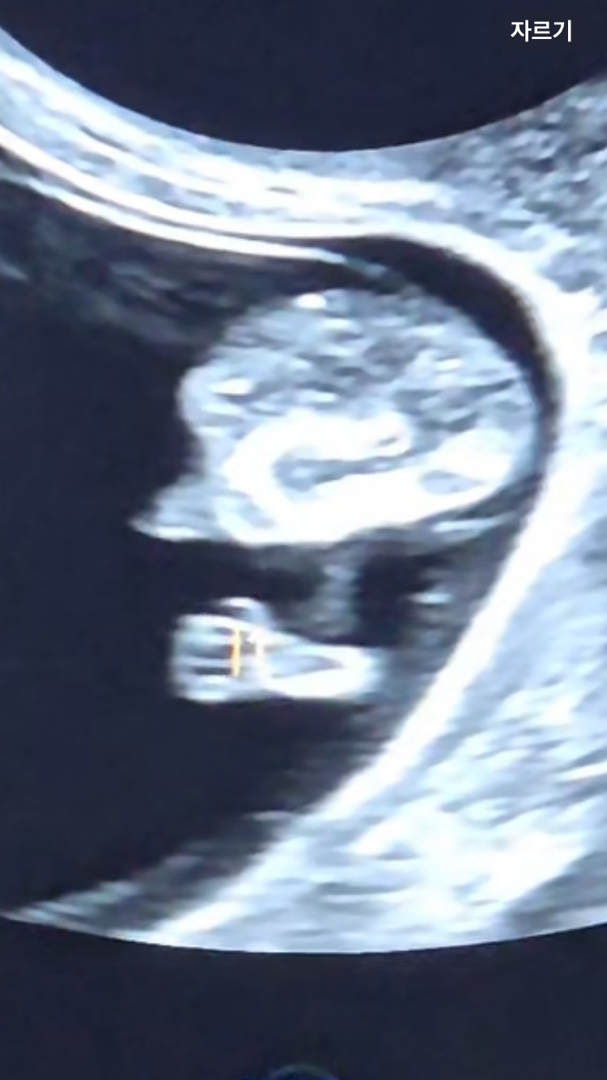

10주차 아기 손가락 6개

10두차 초음파 봤는데 아기 손가락이 6개로 보여요..! 이게 맞나요..?ㅠㅠㅜ 의사쌤도 손가락 5개 세주시고 엄지는 각도가 달라요~ 하셨는데 순간 손가락은 5개인걸 잊으신건지 별말씀은 없으셨어요 저도 그 순간에는 생각못했다가 나중에 초음파 영상 돌려보다가 발견했네요...